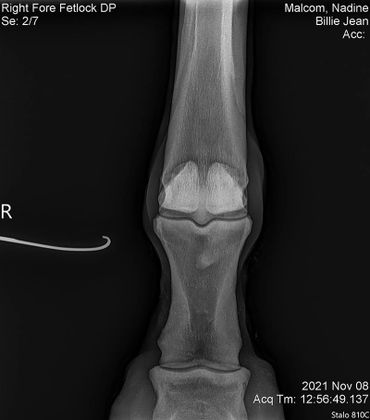

The only issue I'm still working on with her is that she still doesn't like to have a saddle put on her back. Once it's on she's good to go. I've had this mare checked for everything! She got scoped for ulcers, checked for kissing spine, her knees x-rayed since she's a little over the knee and her coffin/ fetlock x-rayed. She's totally fine! I assume that this poor girl was probably ridden in a really poor fitting saddle for years which brought her great uncomfort. I believe over time she will eventually get over this but I can't stress enough that patience is required while saddling her!

BJ also had hr knees, fetlock and coffin joint x-rayed on July 7, 2022. Her vet bill was $185.

We did a full wellness and lameness exam and everything looked pretty good. She showed some soreness in her right front fetlock so we did some x-rays but nothing really to see that would raise concern. We also did x-rays on her stomach and it showed she has some sand which we have been treating with Sand Clear.We didn't do x-rays on her knees. Dr. Johnson said she's probably got some fluid in there because it looks like she used to hit her knees on something a lot so we are rubbing some DMSO on it to relieve some of the swelling.Billie Jean also got a dental float. After examining her teeth closer it turns out she is more like 18-20 years old.